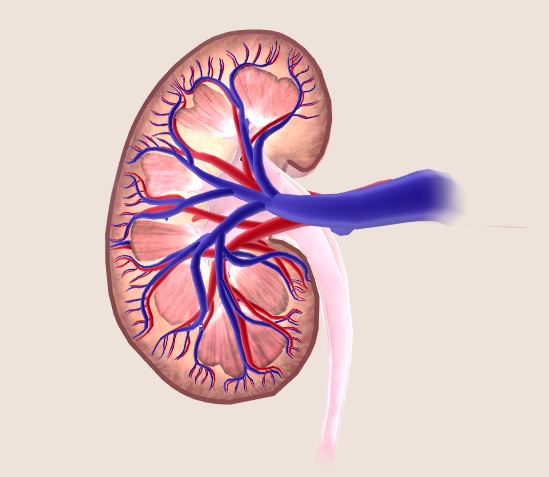

وظایف کلیه ها در بدن. و دخالت این چهار مایع را در کلیه حالات بدنی. شکل زیر عکس واقعی کلیه انسان را نشان می دهد. اگر عملکرد آن ها کم شود نیاز به دیالیز پیدا می کنند.

در هر ساعت کلیه های بدن انسان حدود ۷ لیتر مایع را از خون جدا می کنند این مایع را تصفیه کرده و مواد مفید و سودمند آن را به خون بازمی گردانند و مواد مضر آن را از راه میزنای به مثانه می فرستد تا دفع شوند. کجای بدنتان درد می کند مراجعه کنید آیا کلیه تان درد می کند درد کلیه در اثر عفونت کلیه یا آسیب رسیدن به آن ایجاد می شود. اما کار و وظیفه کلیه ها در بدن چیست بیا یاد بگیریم. زمانیکه کلیه ها بدرستی فعالیت کنند مواد زائد از بدن داخل ادرار ترشح می شوند همچنین کلیه ها در تنظیم سایر مواد معدنی در بدن مانند.

کلسیم و فسفر که برای تشکلی استخوان لازمند کمک می کنند مواد. کلیه ها با تولید ادارد در دفع مواد زاید تعادل الکترولیتی تنظیم هورمونی تنظیم فشار خون و هوموستازگلوکز نقش دارند. آناتومی کلیه انسان در بدن انسان به این شکل است که کلیه ها دو عضو لوبیایی شکل در دستگاه ادراری بوده و به دفع مواد زائد به صورت ادرار کمک می کنند. یکی از مهم ترین وظایفی که کلیه ها در بدن بر عهده دارند پاک کردن و تصفیه خون از زباله هاست.